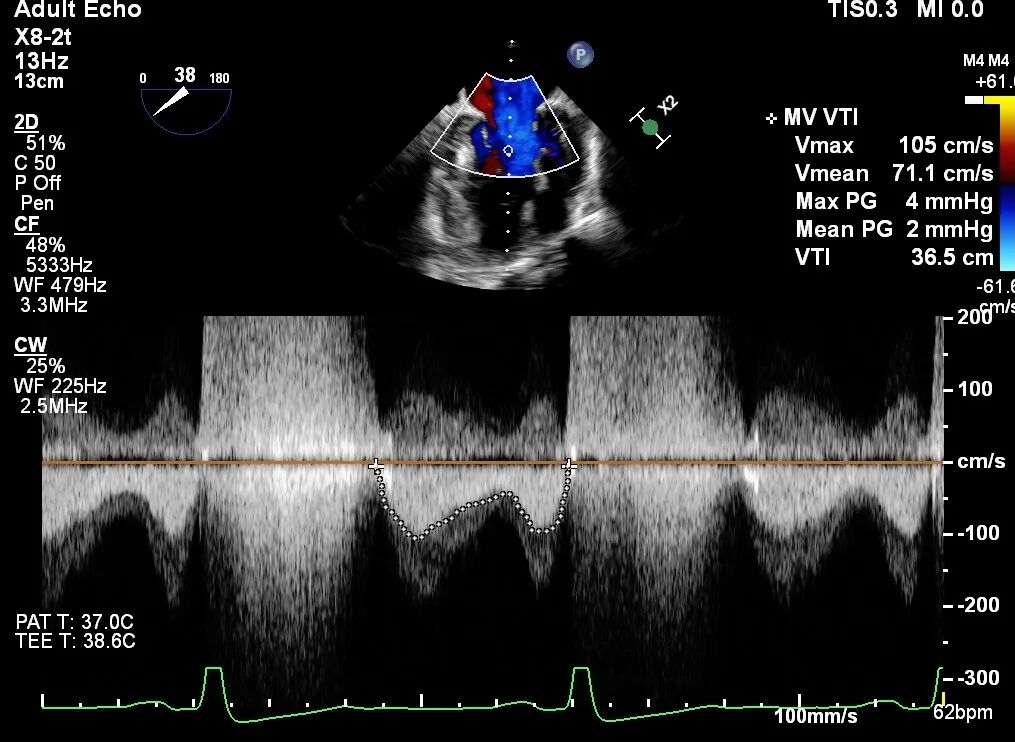

术前TEE评估

原发性MR,交界C1区脱垂,反流程度4+;二尖瓣瓣口面积3.88cm²,平均跨瓣压差2mmHg;二尖瓣前叶(A1)长度16.2mm,二尖瓣后叶长度(P1)长度9.9mm,脱垂高度6mm。